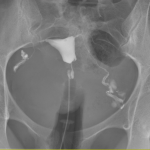

Vous vous demandez quels types de sensations vous pourriez éprouver lors d’un examen d’hystérographie ? Voici les aspects importants de cette procédure, vous fournissant des informations essentielles pour vous préparer au mieux et comprendre ce à quoi vous attendre.